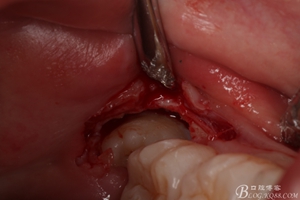

圖6.麻醉效果確定后,在37的近中做垂直松弛切口+遠中水平切口

圖7. 遠中的水平切口